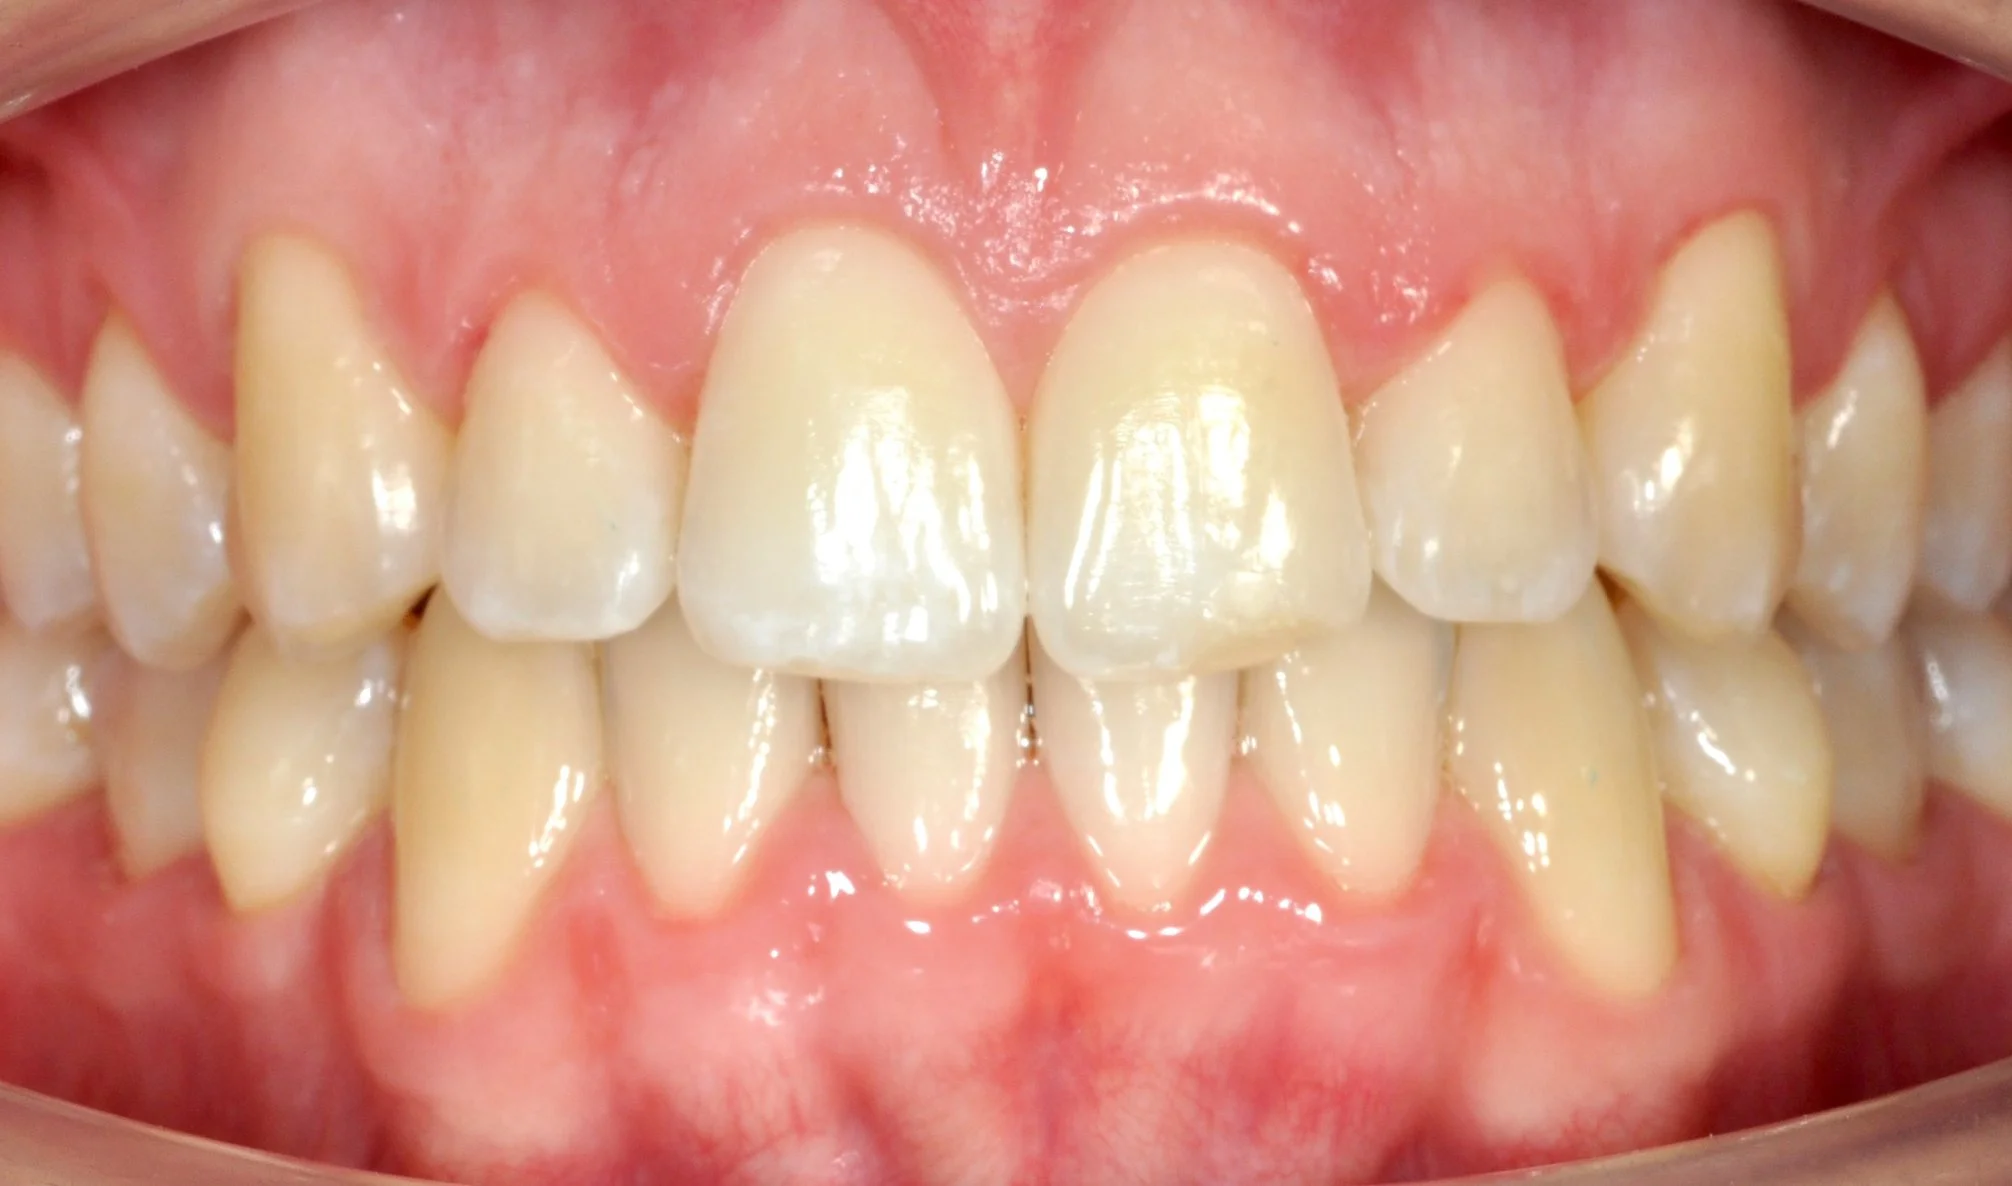

PRIMA

DOPO